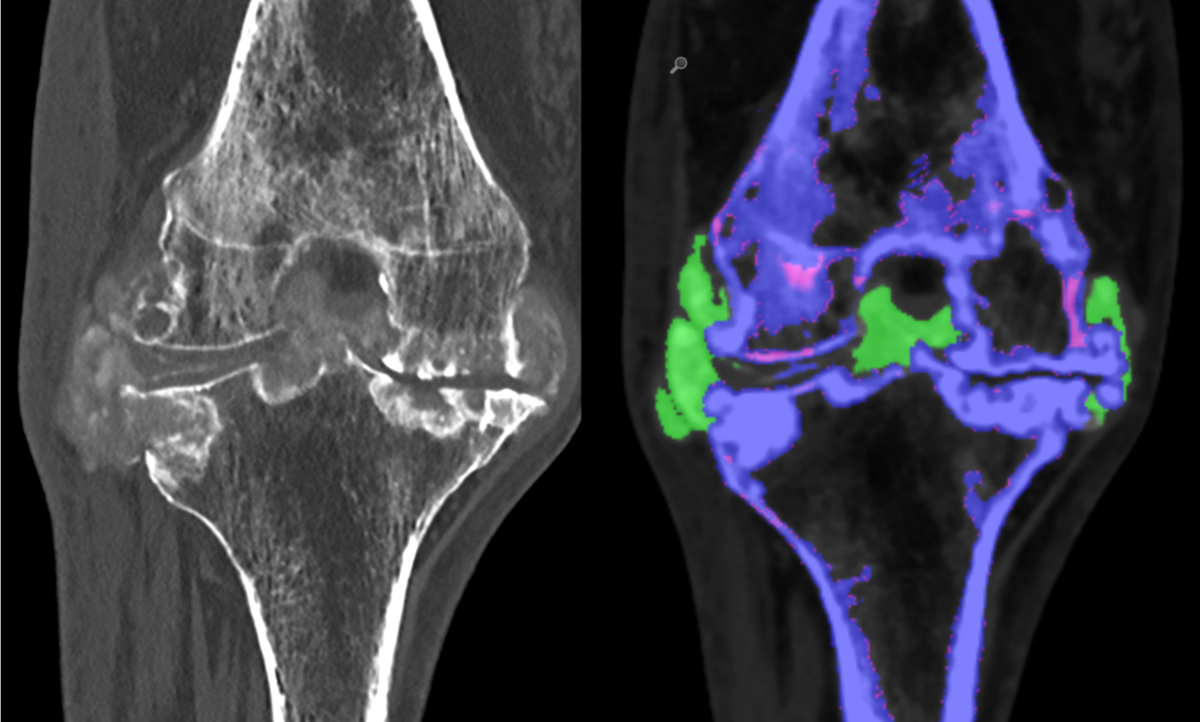

Die Analyse von Spektraldaten im Photon-Counting CT ermöglicht die Darstellung von Uratablagerungen (Harnsäurekristallen). Die Abbildung zeigt ein Kniegelenk mit Gichtarthropathie, Harnsäurekristalle erscheinen grün.